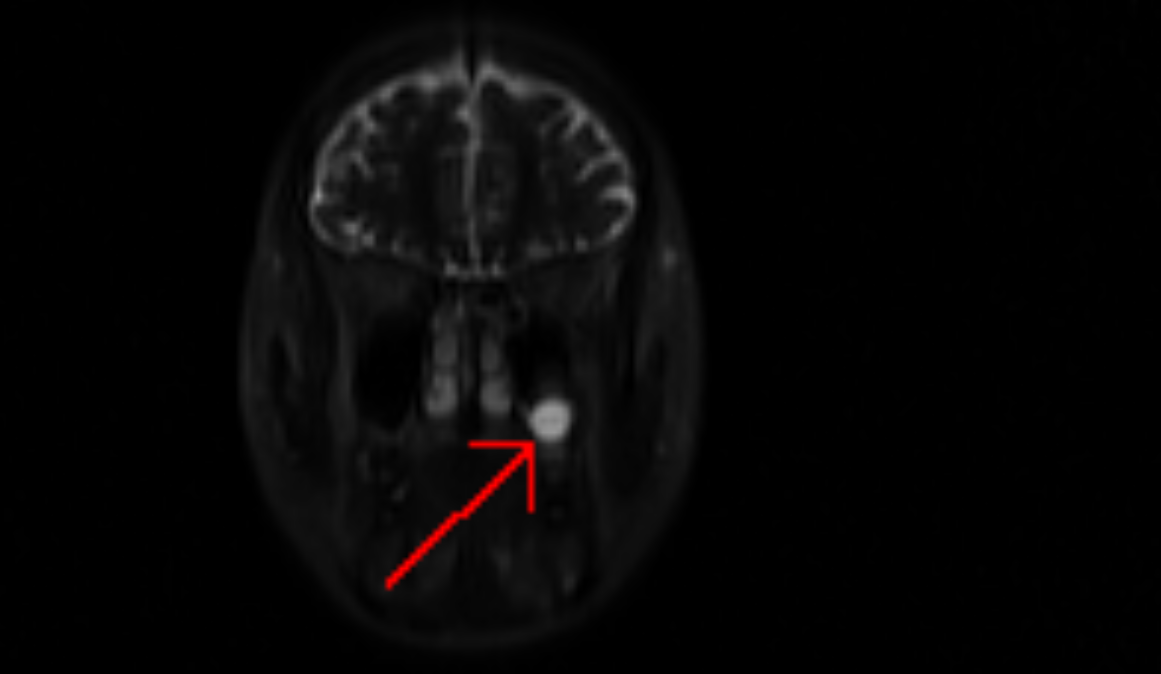

• Finally, I have a mucous retention cyst right behind my left cheek.  This was a surprise finding as I didn't have any symptoms at all. This may cause me to have sinus pain or pressure during a particularly bad run of allergies or infections, but otherwise, it could go away on its own. Or, it could grow.

Face scan showing mucous retention cyst on my left side